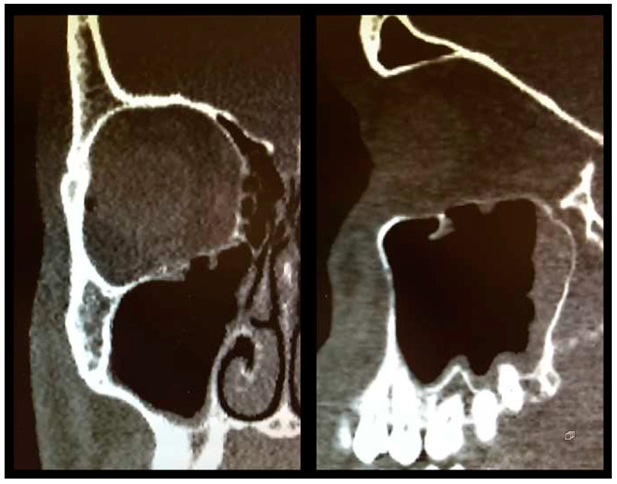

Figure 3.

Postoperative CT scan following OFF reduction and placement of Ethisorb® ((left) coronal view, (right) sagittal view).